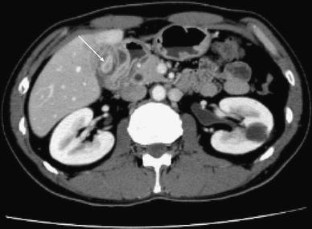

Xanthogranulomatous cholecystitis: the use of preoperative CT findings to differentiate it from gallbladder carcinoma

All patients underwent preoperative CT scanning. The CT features analyzed were: the presence of intramural hypoattenuated nodules or bands, mucosal line, the patterns of wall thickening and enhancement, and the presence of stones in the gallbladder. The variables of the CT findings with XGC were analyzed using multivariate logistic regression analysis.

Intramural hypoattenuated nodules were observed in 21 patients (65%) with XGC, but in only six patients (29%) with gallbladder carcinoma (< 0.01). The mucosal line was observed in 27 patients (84%) with XGC and in only four patients (19%) with gallbladder carcinoma (< 0.0001). Gallstones were noted in 24 patients (75%) with XGC and five patients (24%) with gallbladder carcinoma (< 0.001). There was no significant difference in the pattern of gallbladder wall thickening (diffuse or focal) and the presence of changes outside the gallbladder. Multivariate logistic regression analysis revealed from the CT features that the enhanced continuous mucosal line (= 0.0013) and the presence of gallstones (= 0.0072) were independently correlated with XGC.

CT features of the enhanced continuous mucosal line in a thickened gallbladder wall, together with gallstones in a patient with chronic gallbladder disease, are highly suggestive of XGC. Accurate diagnosis of XGC may therefore indicate the need to select a less aggressive surgical approach.